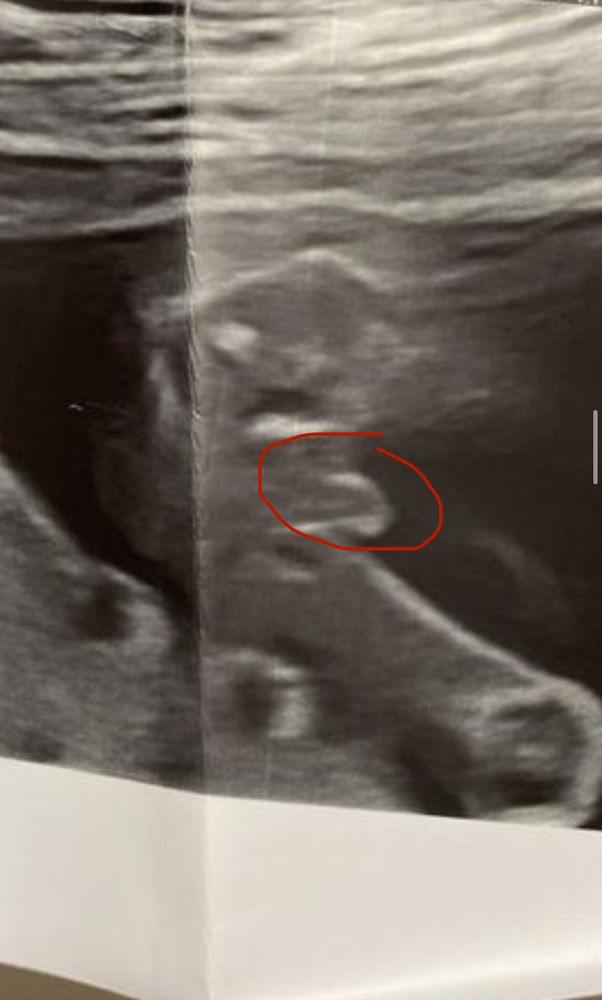

Вот же)))

"Он смотрит прямо в душу..."

Отличный кадр поймали, даже если это не голова)) без сарказма, честно, реально классно))